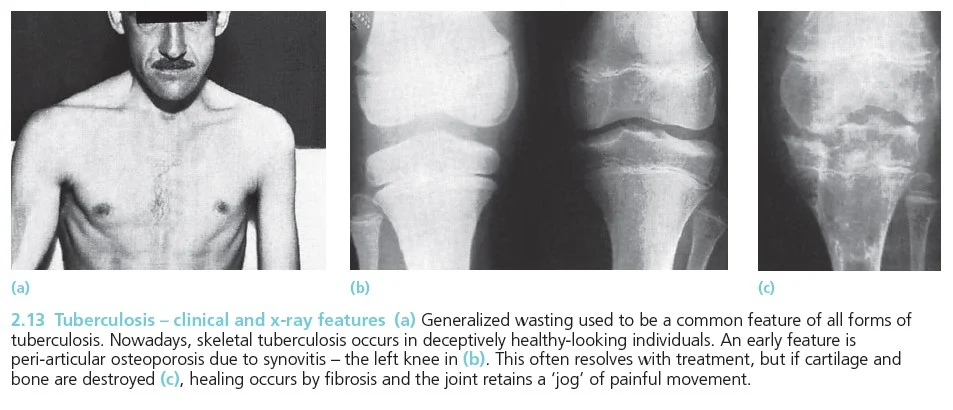

- Joints: usually monoarticular

- Peri-articular osteopenia

- Subchondral and peripheral erosions affecting both sides of the joint

- Loss of joint space